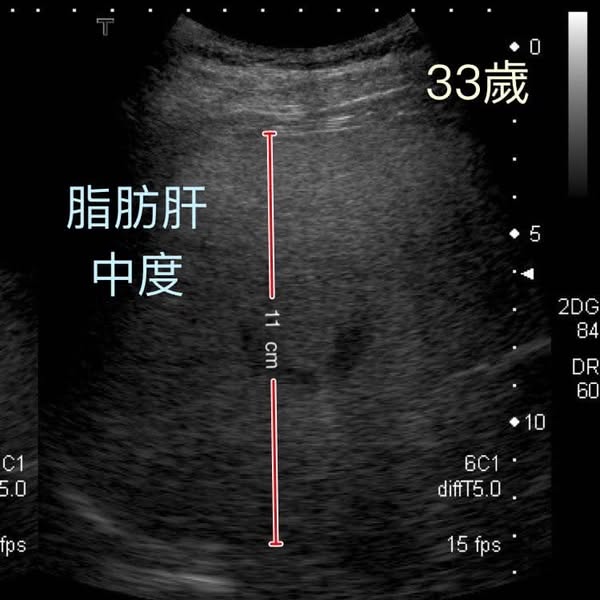

錢政弘醫生表示,該名男病患現年48、49歲,早在15年前,即33歲時,就因體重過重(95公斤),被診斷出患有中度脂肪肝。當時他的肝指數過高,但沒有B型或C型肝炎,也沒有飲酒或吸煙習慣,診斷為「非酒精性脂肪肝炎」。

錢醫生指出,一般而言,脂肪肝惡化為肝硬化需要20至30年,但這位病患卻只用了短短15年。他曾持續追蹤病情一年,但之後便自行中斷覆診。直到去年,他因吐血緊急送院,經檢查才發現已是嚴重肝硬化,並伴隨食道靜脈曲張出血及大量腹水。